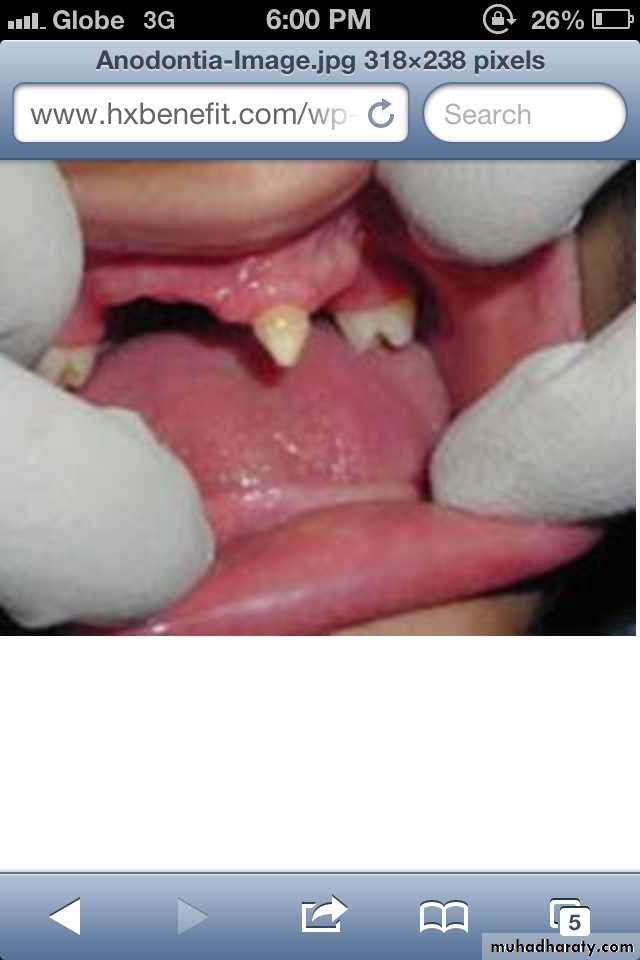

Anodontia : the failure of all teeth to develop .

Pseudoanodontia: when teeth are absent

clinically because of impaction or delayed eruption.

False Anodontia: when teeth have been

exfoliated or extracted.

Anadontia